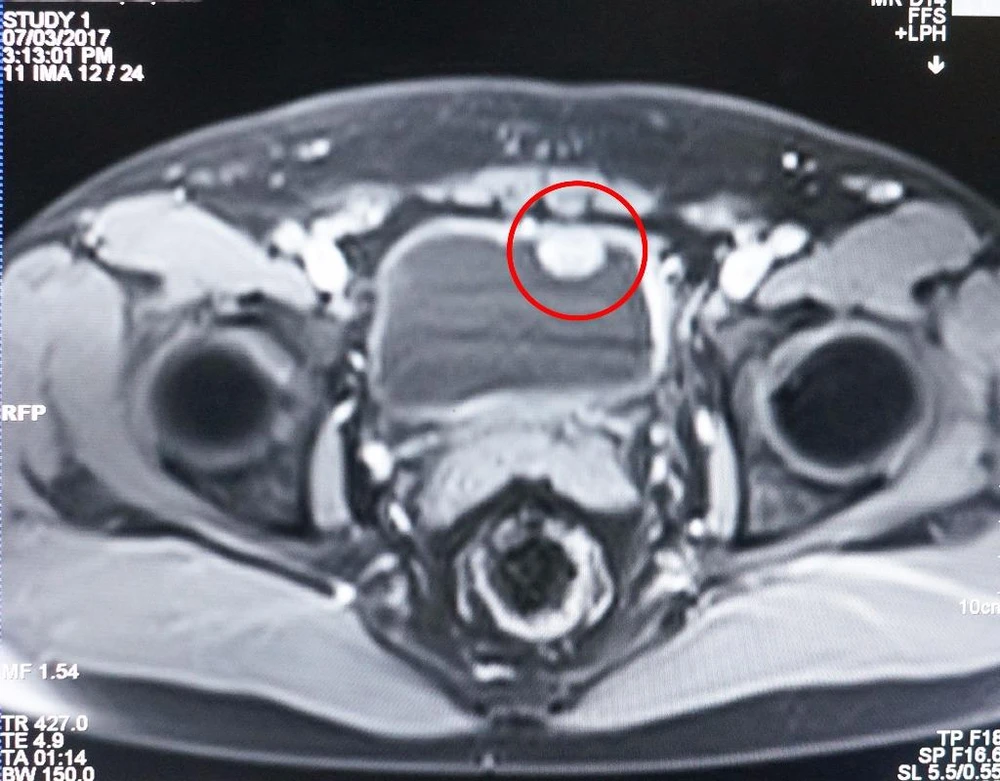

Kết quả chụp MRI cho thấy khối u xâm lấn qua lớp cơ bàng quang.

Kết quả chụp MRI cho thấy khối u xâm lấn qua lớp cơ bàng quang. Ảnh: LÊ PHỤNG

Qua khám lâm sàng và soi bàng quang sinh thiết, chụp MRI, các bác sĩ xác định khối u đã xâm lấn qua lớp cơ bàng quang. Để hạn chế tái phát, giảm biến chứng và giúp ông Đ có thể tiểu tiện bình thường sau mổ, các bác sĩ thực hiện phương pháp phẫu thuật nội soi cắt bỏ bàng quang và tái tạo lại bằng ruột non của bệnh nhân.